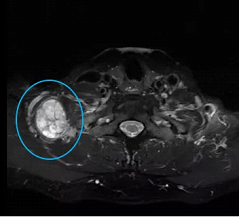

张先生和赵先生住院以后都做了颈部的磁共振检查,检查结果显示张先生的肿块长在了下颌角的边上,肿块还包绕着颈部的大血管。而赵先生的肿块是从臂丛神经上长出来的。

赵先生颈部磁共振